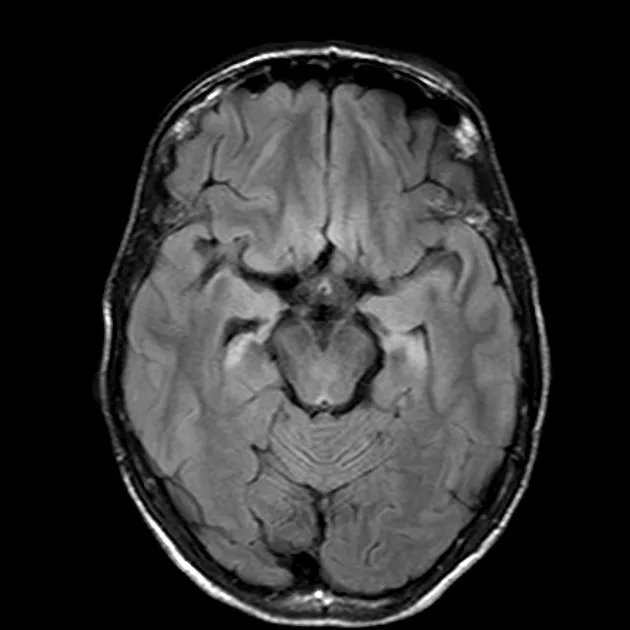

Prion Diseases (e.g., CJD):

- Patho: Misfolded PrPSc.

- Features: Rapid dementia, myoclonus.

- Dx: EEG (periodic sharp waves), CSF (14-3-3 protein), MRI (DWI/FLAIR hyperintensities).